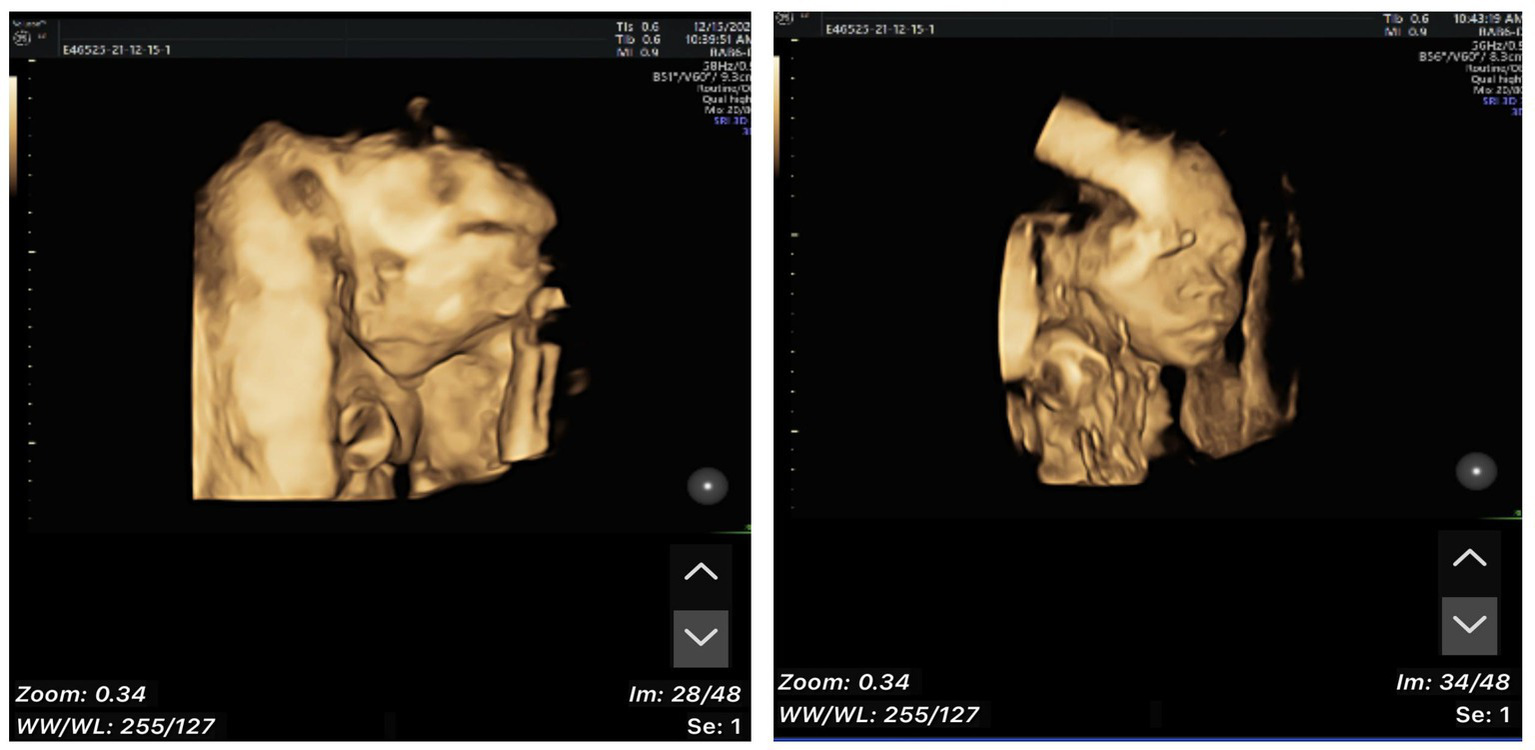

A 33-year-old primiparae was admitted in spontaneous labor to the labor and delivery service of the Second Affiliated Hospital of Wenzhou Medical University (Wenzhou, China) at 40 weeks of gestation. The patient was in good health during pregnancy, except for gestational diabetes mellitus. She had a routine obstetrical ultrasound at 21 weeks gestation, which revealed an abnormal bean-like dilation of the intra-abdominal umbilical vein, and umbilical vein thrombosis was suspected (Figure 1). Table 1 shows the umbilical vein flow pattern from 21 weeks to 40 weeks. Figure 2 shows the fetal color ultrasound image at 21 weeks. The fetal system ultrasound examination was performed at 21 weeks gestation and showed no abnormalities in the fetal biometric measurements, head, facial features, spine, chest, heart, diaphragm, stomach, abdominal wall, kidneys, bladder, forearm bones, lower leg bones, hands, feet, and bilateral adnexal regions of the pregnant woman. The placenta was located on the posterior wall of the uterus with normal thickness and grade, and the maximum depth of amniotic fluid pool was within normal range. The umbilical cord had a normal morphology with two umbilical arteries and one umbilical vein, and normal blood flow waveform in the umbilical artery. There was a local dilation of the intra-abdominal segment of the umbilical vein, but with normal blood flow parameters. Subsequently, she was scheduled for close follow-up with prenatal ultrasound every 2 weeks. Repeat ultrasound examination showed that the hyperechoic oval structure enlarged gradually, but there were no obvious abnormalities in umbilical cord blood flow, fetal growth or fetal heart monitoring. The delivery was uneventful, and an apparently healthy female infant weighing 2,830 grams was delivered. Apgar scores were 10 at 1 min and 10 at 5 min. The amniotic fluid was clear, and the placenta was delivered intact. No gross placental lesions or umbilical cord anomalies were identified. An abdominal ultrasound was performed soon after birth, which suggested thrombosis in the umbilical vein and portal vein. The baby was subsequently transferred to the neonatal intensive care unit (NICU) for clinical monitoring and observation.

Figure 1

Abnormal bean-like dilation of the intra-abdominal umbilical vein suggestive of umbilical vein thrombosis at 21 weeks of gestation.

Figure 2

Fetal color ultrasound image at 21 weeks.